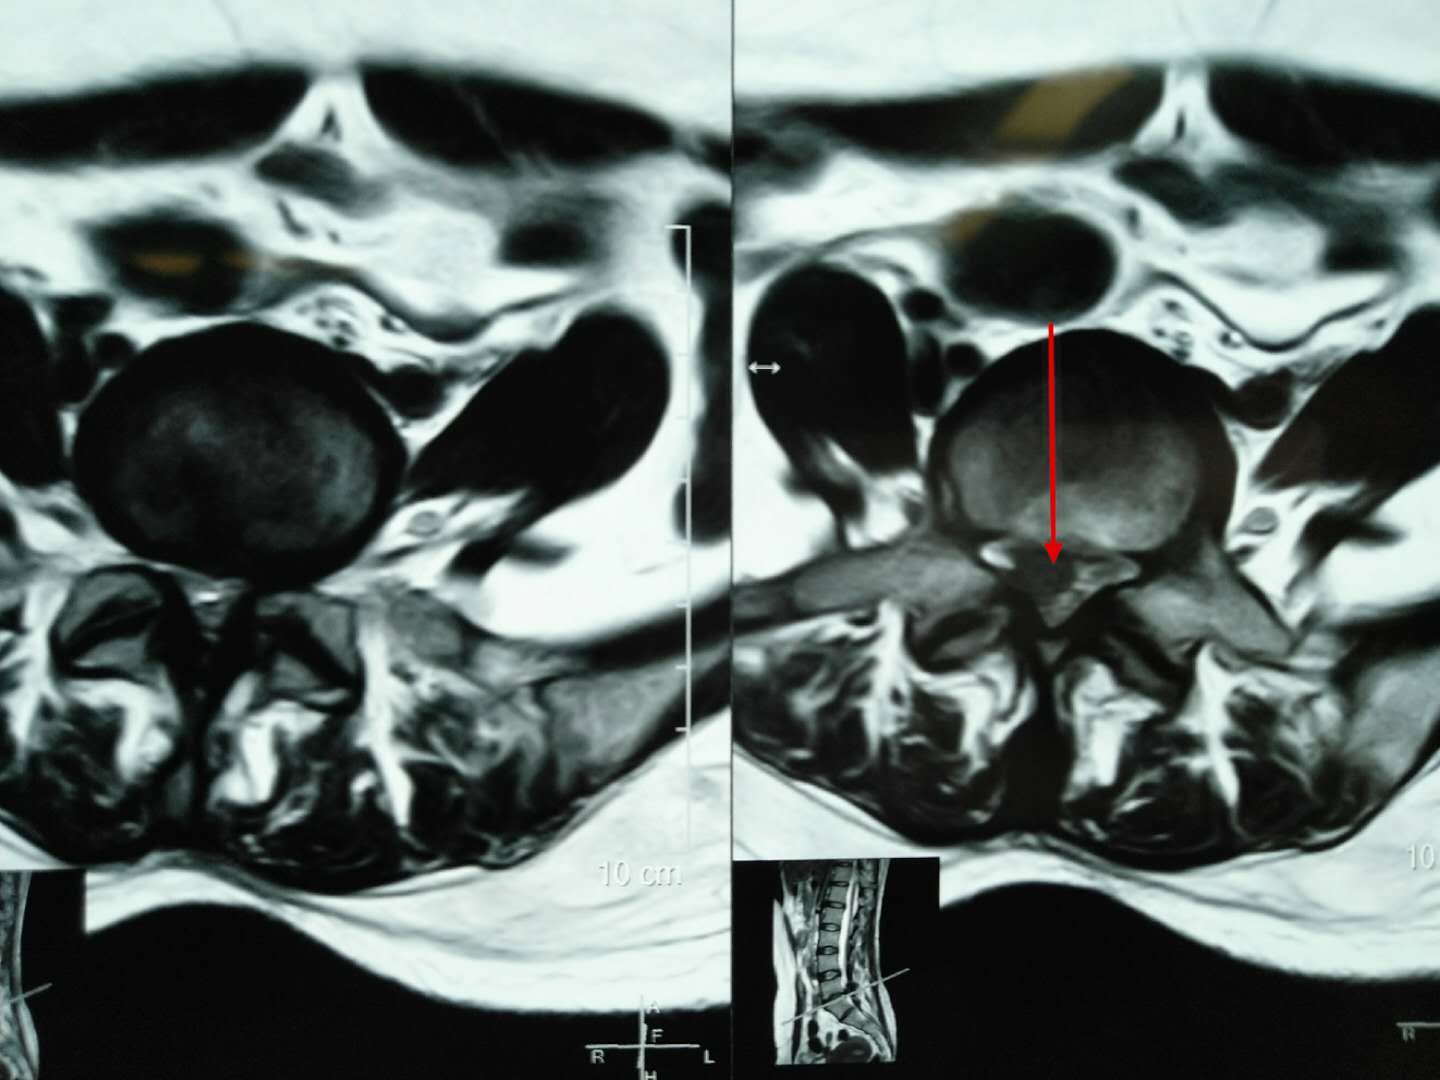

从术前的腰椎磁共振我们可以看到腰椎向下脱垂游离的巨大间盘突出,压迫右侧神经根,我们给她做了后路脊柱内镜下腰椎间盘摘除术。

术后第二天复查腰椎磁共振我们可以看到脱垂的间盘组织被完整的摘除,术后当即患者的症状就消失了,可谓立竿见影。